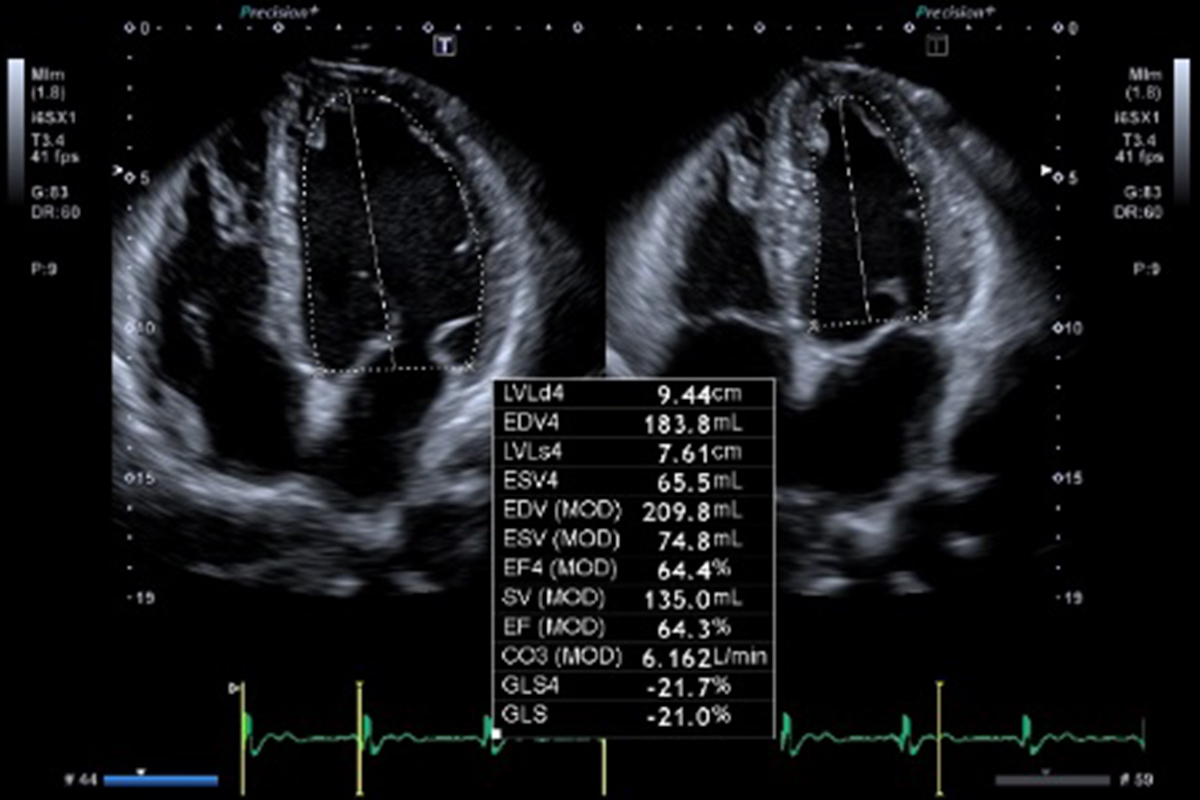

Auto-EF with Global Longitudinal Strain (GLS)1

- Automatic integration of Strain measurements with Ejection Fraction and volume measurements

- No need to enter dedicated strain packages

- Aplio systems automatically calculate Ejection Fraction, LV volumes and now GLS.

- Auto EF with Full-assist function is powered by artificial intelligence2

1Available on Aplio i-series / Prism Edition and a-series

2Available on Aplio i-series / Prism Edition

Automatic integration of Strain measurements with Ejection Fraction and volume measurements without the need of dedicated strain packages.